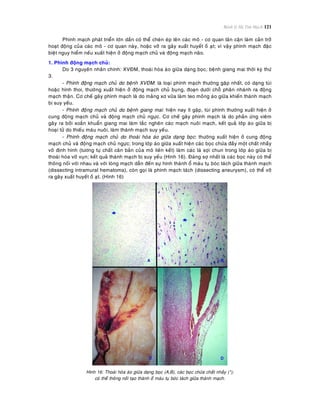

huyeát ñoäng neâu treân.

- Söï taêng tính thaám thaønh maïch, laø cô cheá chính gaây ra phuø vieâm. Söï taêng tính thaám thaønh